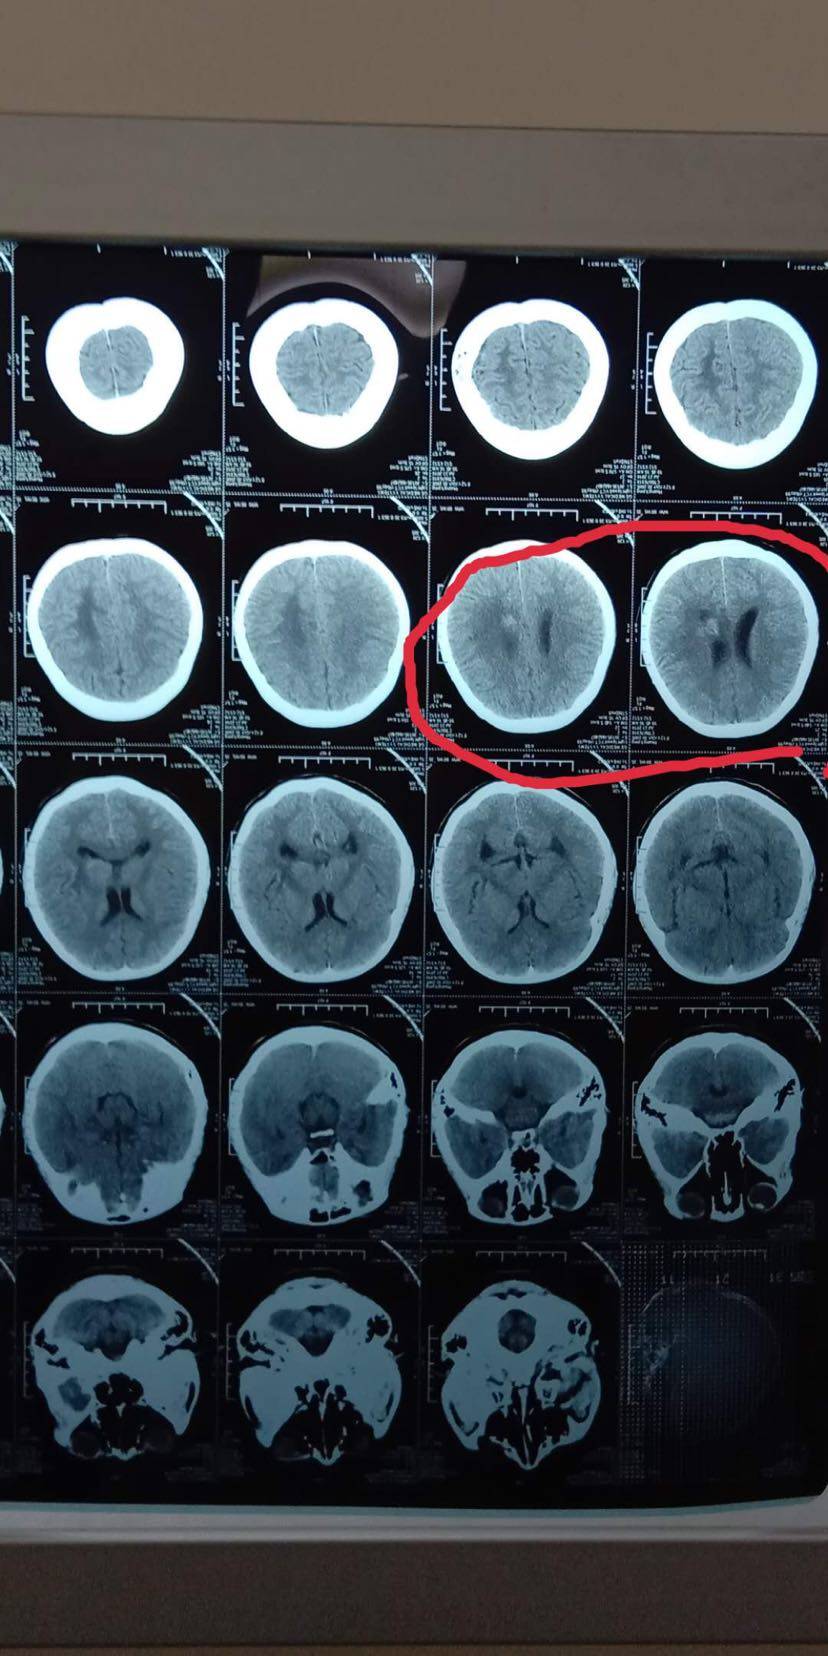

第二步:用放射性碘125粒子,通过三维立体成像技术(3D影像),铺助3D建模精准植入到肿瘤内部,在内部持续杀死肿瘤,不伤害正常细胞。

把河里的鱼捞完了是不是就可以万事大吉了呢?不是!河里的鱼卵还在,也就是休眠期的肿瘤细胞还在,不处理它,等到合适的时候,它一定会重新长出来。所以采用放射性碘125粒子植入,小型的核导弹精准打击彻底摧毁目标范围内所有的一切生物。